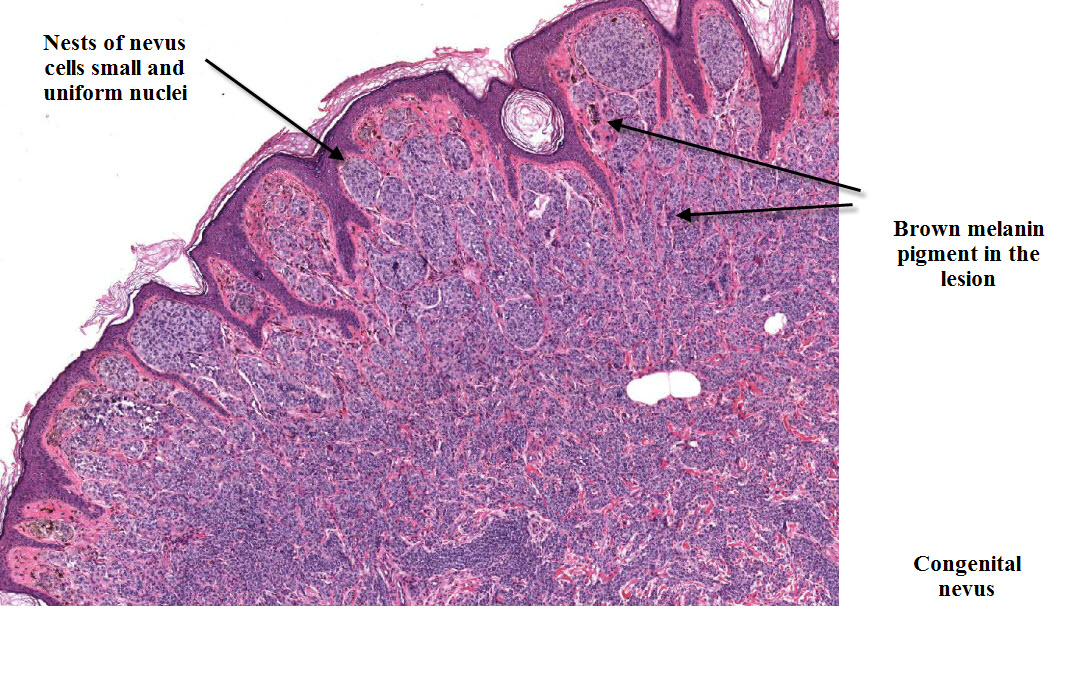

Родинки у детей гистология - фото презентация